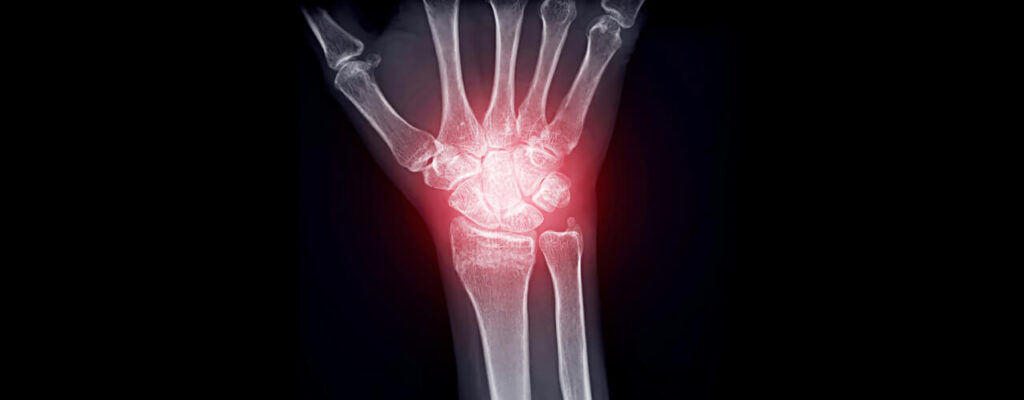

Arthritis can feel like a constant obstacle, making everyday activities challenging and painful. With stiffness, swelling, and discomfort often becoming part of daily life, many patients find themselves searching for a solution that truly works. At , we have proven arthritis treatment options to manage symptoms, improve mobility, and enhance overall quality of life.

Why Arthritis Needs a Comprehensive Approach

Arthritis isn’t just about joint pain—it’s a multifaceted condition that affects the entire body.

Read full blogHow to Manage Joint Inflammation from Arthritis

For 57-year-old Linda (not her real name), arthritis had slowly taken over her life. Once an active gardener and avid walker, she now struggled with daily tasks due to constant joint swelling and pain. Medications offered temporary relief, but the stiffness and discomfort always returned. Frustrated and seeking answers, Linda turned to physical therapy at for long-lasting joint inflammation relief and a return to the activities she loved.

When Joint Pain Becomes Too Much

Linda’s arthritis had progressed over the years, making simple tasks like opening jars or climbing stairs feel monumental.